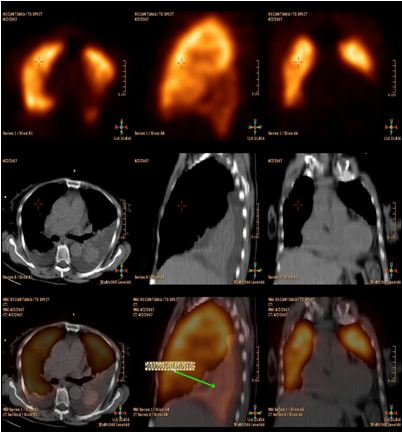

Ghi hình phát hiện các khối u trong phổi, YHHN đã và đang phát triển mạnh. Hiện nay SPECT, SPECT/CT, PET và PET/CT đã cho những hình ảnh định lượng về giải phẫu và chức năng cụ thể, nâng cao hiệu quả chẩn đoán và điều trị. Dưới đây ví dụ vài hình ảnh cụ thể:

PET/CT ghi hình khối u hoaị tử .

SPECT/CT ghi hình tràn dịch màng phổi (Trên cùng : Hình của SPECT, Giữa : Hình của CT, Dưới :Phối hình giữa SPECT với CT. )